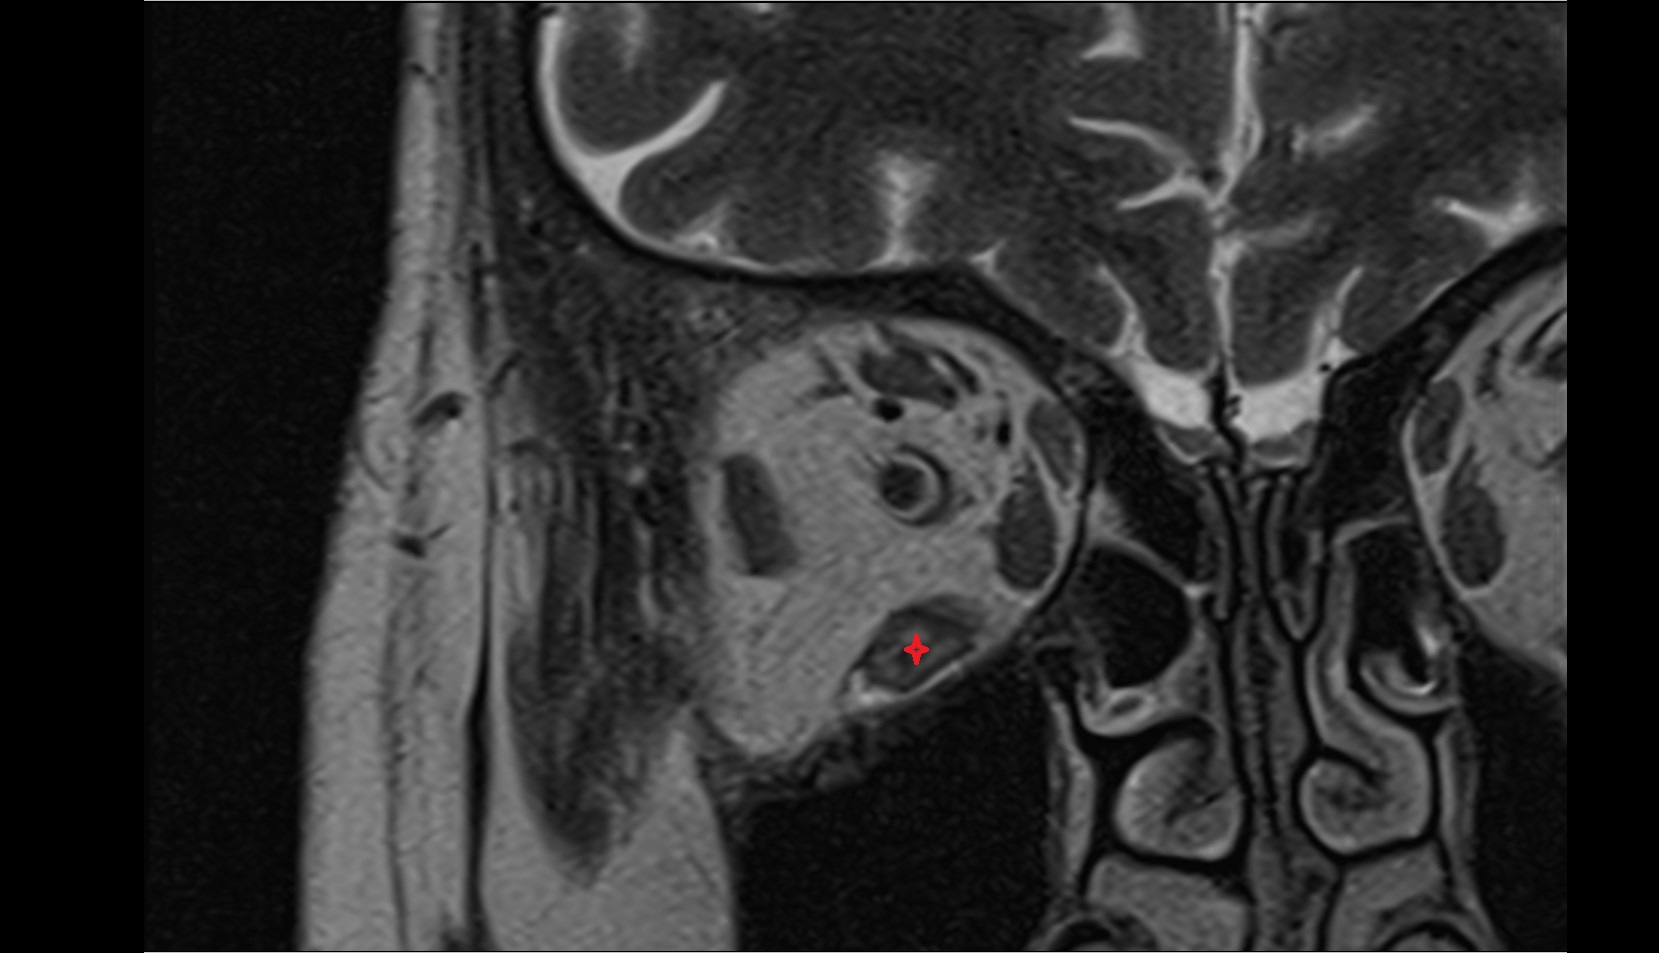

- Placenta

- Uterus (pregnancy)

- Amniotic fluid

- Umbilical cord

- Fetal brain

- Fetal caudate nucleus

- Fetal thalamus

- Fetal pons

- Fetal cerebellum

- Fetal occipital lobe

- Fetal temporal lobe

- Fetal parietal lobe

- Fetal frontal lobe

- Fetal third ventricle

- Fetal fourth ventricle

- Fetal lateral ventricle